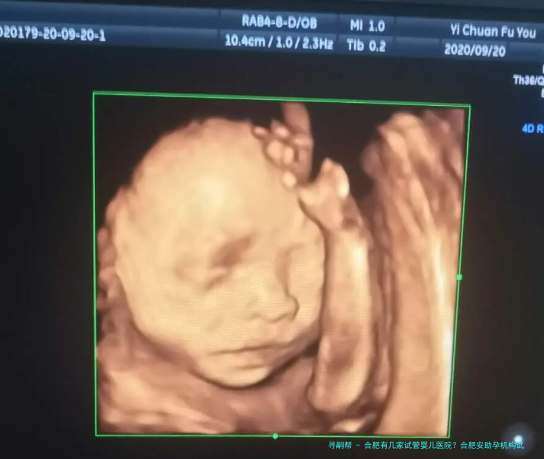

合肥有几家试管婴儿医院?合肥安助孕机构试管成功率高吗?

在合肥想做试管婴儿的夫妻越发越多。好在合肥能做试管婴儿的医院有许多,目前合肥有四家医院可以选择。面对合肥4家可以做试管婴儿的医院,很多夫妻会问合肥哪家医院好?在合肥做试管婴儿的费用是几许?接下来让我带所有人一起了解一下吧!